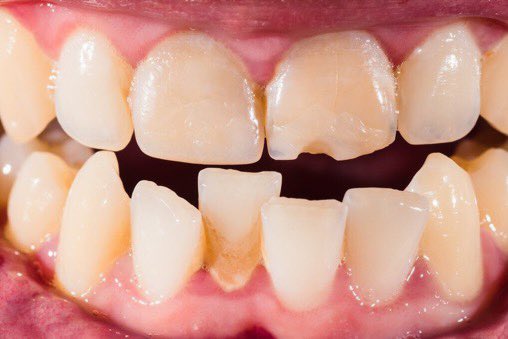

اللثة السليمة:

لكي نتعرف على اللثة المريضة يجب أولا معرفة الصحية أو السليمة ونعرف الاختلافات البسيطة بين جميع الأعراق.

اللثة السليمة لونها زهري(غالبا)ملتصقة بالأسنان لامعة (غالبا)لا تنزف عند اللمس أو التفريش أو بدون سبب/بعض الناس(الملونين)لديهم تصبغات سمراء طبيعية(الشرح لاحقا)(٢)